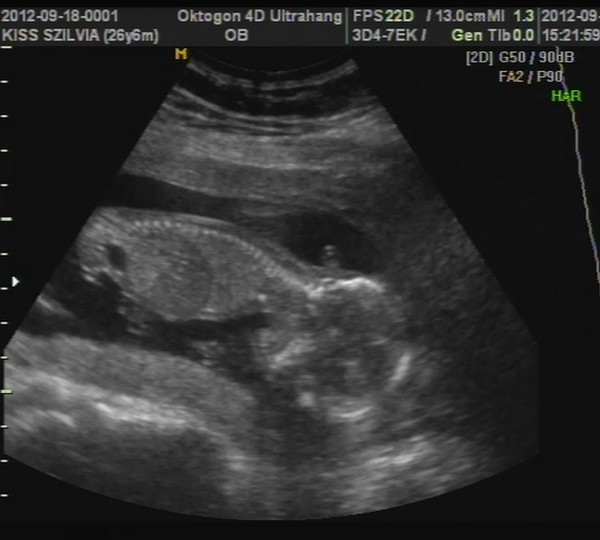

A képek először a babáról. :-) Kép 4d kedvenc :-)

Kép 2d

Kép tappancs

Kép és ott az a pici háromszög a lábikó között a kukac :-)

Édes a kicsikéd!És az a talpacska...enni való!(úgye jólláttom hogy az talpacska?) 8)

Igen az a talpija :-) Sejtheted a kedvenc képem :D